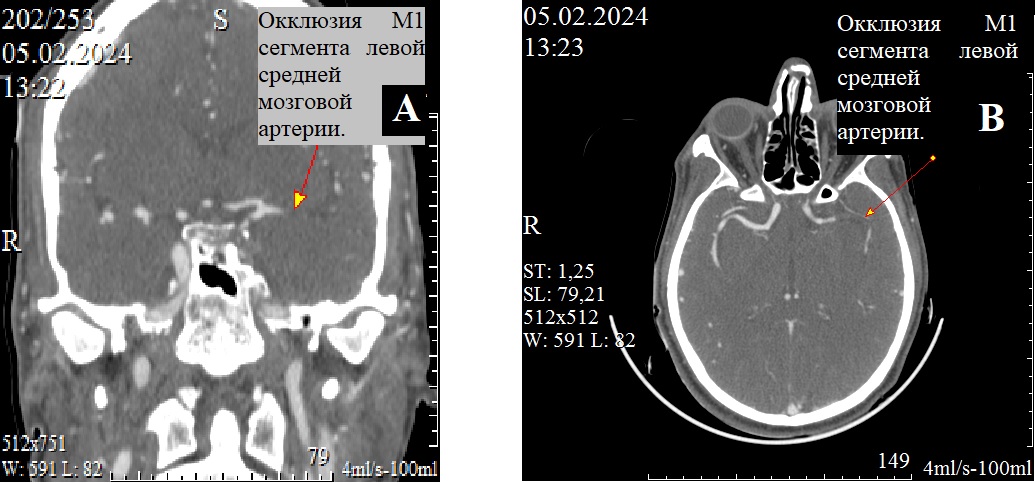

Рисунок 1 - Ангиографические признаки окклюзии М1 сегмента левой средней мозговой артерии